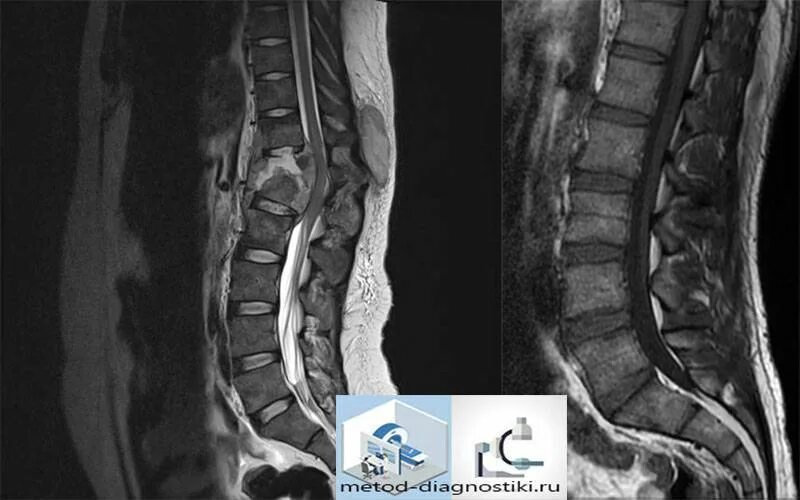

Как делают кт пояснично крестцового отдела